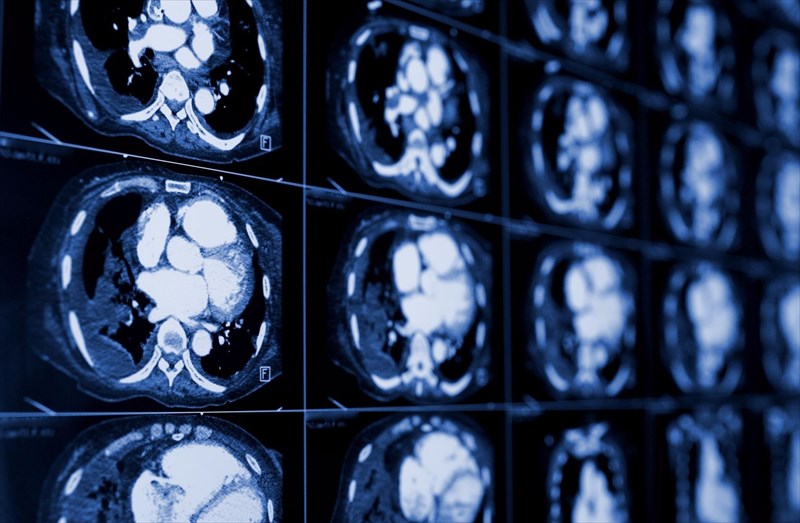

As an imaging technique which can give medical professionals eyes on the inside of the body, CT scans have a variety of different uses, particularly when it comes to evaluating injuries and diagnosing diseases.

A CT scan may be recommended to:

• Check for muscle disorders

• Evaluate bone fractures and joint problems

• Diagnose infections in the body

• Diagnose conditions such as liver problems, emphysema, cancer or heart disease

• Locate tumours or abnormal masses (growths), blood clots and build-up of fluid in the body

• Assess internal structures and blood vessels, as well as internal injury and bleeding